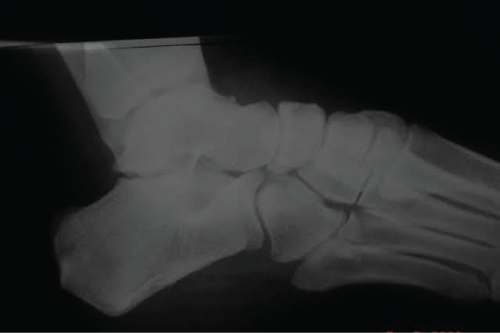

Patient of 39-years-old, female, business woman of the transport branch, was admitted to the emergency room, after suffering a truck fall, reporting that she was wearing high heels at the time of the fall. She presented a sprain in her left foot with severe edema. Normal neurovascular physical examination. An X-ray performed, which showed isolated dislocation of the navicular and rupture of the dorsal talonavicular, calcaneonavicular and cuneonavicular ligaments (Figure 1). No lesion on the posterior tibial tendon reported. According to the AO and Tscherne classification of closed fractures, it was a closed fracture grade 0 (Fr. C 0) [7].

Figure 1: Preoperative X-ray showing isolated dislocation of the tarsal navicular.